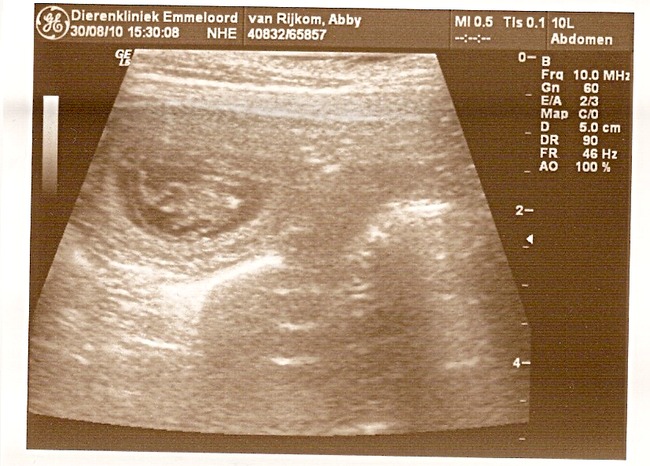

Onze vermoedens zijn bevestigd, Abby is inderdaad drachtig! En hoe...

Op de echo waren 7 levende pups met mooie kloppende hartjes te zien!!!

Hier trouwens de echo foto's:

Oh beetje een kleine foto... Ik zal kijken of ik 'm groter kan plaatsen

We zeiden ook al bij 5 jullie mogen nu wel stoppen hoor maar het ging maar door en door, we hebben allemaal echt iets van 3x getelt en steeds kwamen we op die schrikbarende 7 pups uit

Ja het blijft afwachten, ze kunnen altijd een foutje maken bij zo een echo. Maar heb meegeteld en er ook 7 gezien dus zal spannend worden